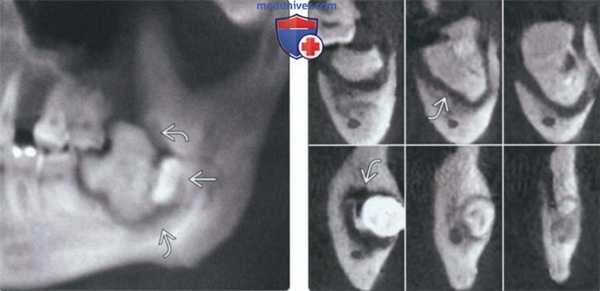

(Слева) На панорамной реформатированной КЛКТ вокруг коронки смещенного третьего моляра нижней челюсти определяется инфицированная частично прорезавшаяся смешанная одонтома. Обратите внимание на широкий гиподенсный ободок возле зоны остеосклероза. Причиной инфекции может стать контакт с жевательной поверхностью моляра-антагониста.

(Справа) На профильных срезах (КЛКТ) у этого же пациента определяется инфицированная смешанная одонтома с рваными контурами и склерозом окружающей костной ткани.